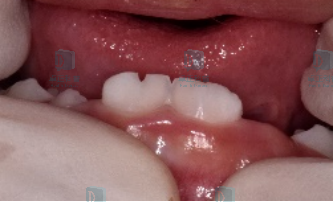

双排队形

现在很多孩子换牙的时候会出现“双排牙”:新牙和旧牙排成两排,同时出现在口腔里。这种情况叫做乳牙滞留,俗称“双排牙””,简单来说就是旧的乳牙还没来得及脱落,新的恒牙就已经迫不及待的长出来了。

图片

出现双排牙,提前拔除滞留的乳牙有利于新牙尽早的排齐,同时也便于清洁尤其是上颌的双排牙,应尽早拔除滞留乳牙,避免造成前牙反颌。因此,如果孩子出现了双排牙情况,是时候去拜访一下牙医了。